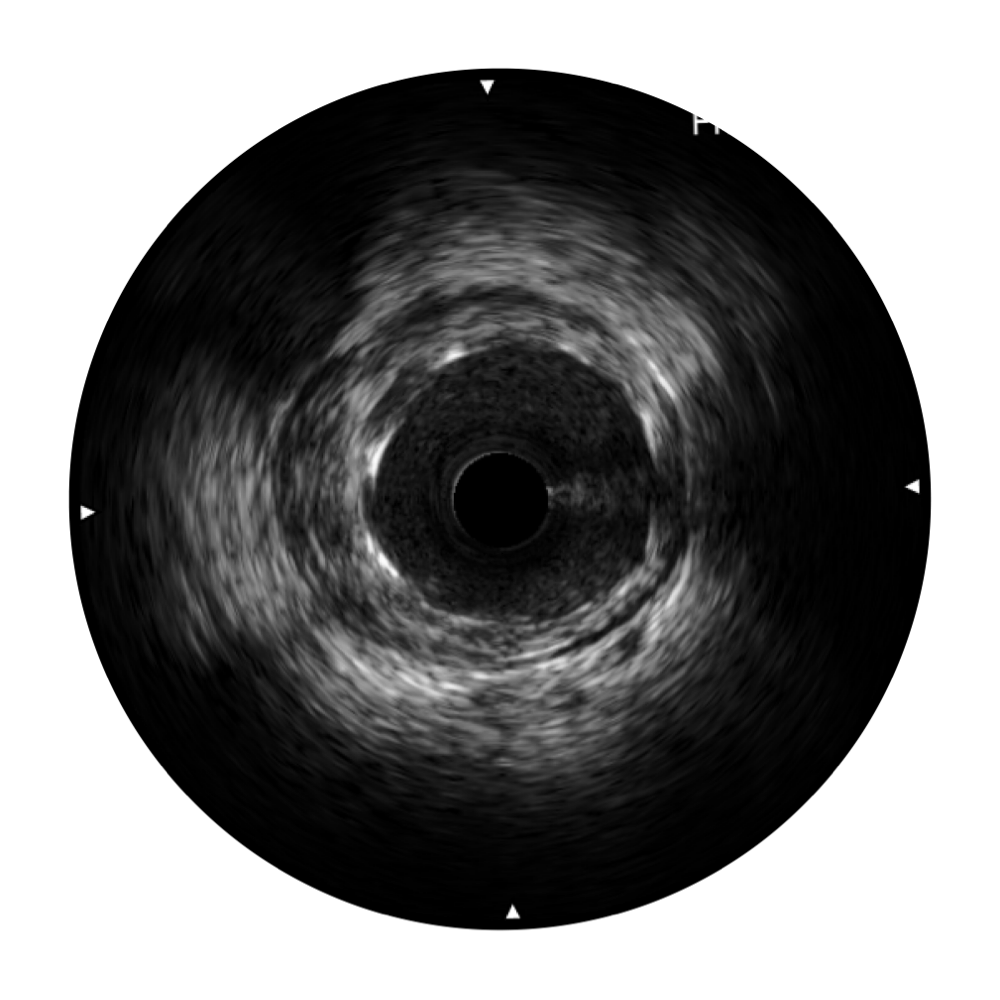

開(kāi)立寬頻IVUS圖像

對(duì)比傳統(tǒng)IVUS導(dǎo)管成像,開(kāi)立寬頻IVUS圖像的近場(chǎng)支架梁顯影更細(xì)膩,遠(yuǎn)場(chǎng)中膜外血管仍清晰可辨,兼顧遠(yuǎn)中近,兼顧分辨力與穿透深度